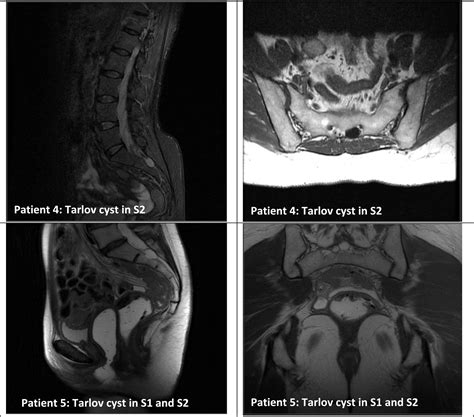

Diagnosing a symptomatic Sacral Tarlov Cyst requires a comprehensive approach. Because they are soft-tissue structures, they are best visualized using high-resolution Magnetic Resonance Imaging (MRI). A radiologist or neurosurgeon will look for specific markers, such as the location, size, and the degree of bone remodeling (erosion) occurring in the sacrum, which indicates that the cyst has been present for a significant period.

In addition to imaging, physicians may conduct a detailed neurological examination to map out sensory deficits and assess muscle strength. Some clinics may also utilize specialized imaging, such as a Cine-MRI, to study the flow of cerebrospinal fluid around the cyst.